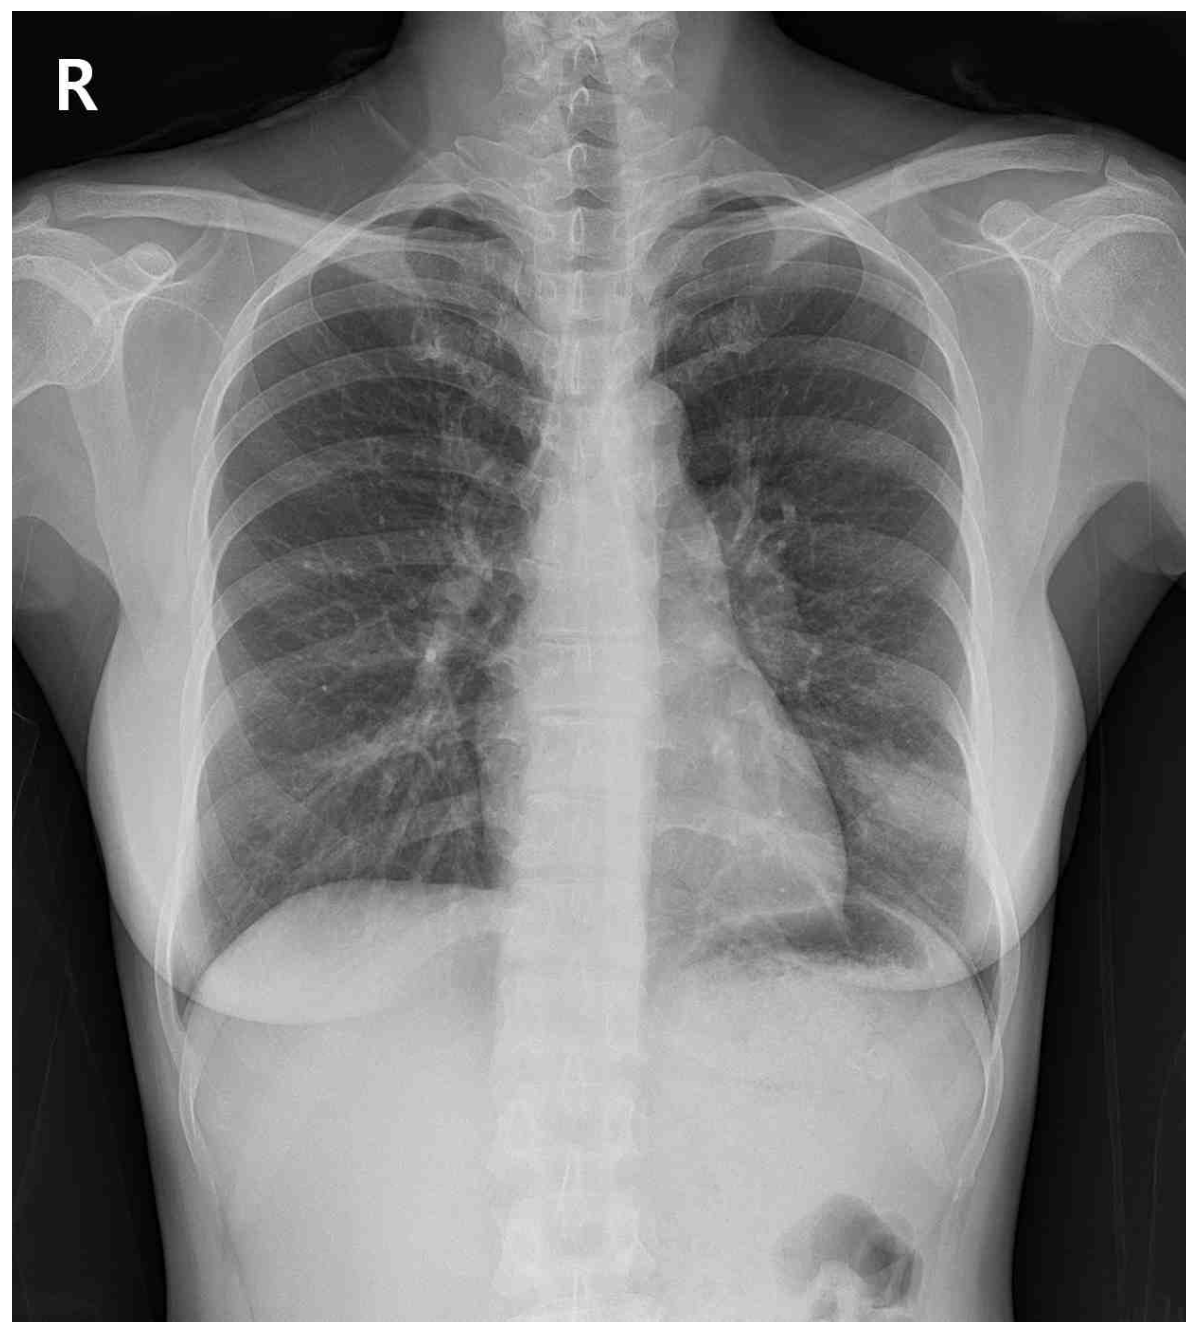

55세 여자가 1개월 전부터 오른쪽 가슴이 아파서 병원에 왔다. 2개월 전부터 심하게 피로했으며 2주 전부터 오른쪽 겨드랑이에서 덩이가 만져진 후 빠르게 커졌다고 한다. 35갑•년의 흡연자 이다. 혈압 110/80 mmHg, 맥박 68회/분, 호흡 16회/분, 체온 36.5 °C이다. 오른쪽 겨드랑이가 부어 있으며 만졌을 때 단단하면서 압통이 관찰된다. 심음과 호흡음은 정상으로 들린다. 가슴 X선 사진과 가슴 컴퓨터단층촬영 사진이다. 혈액 검사 결과는 다음과 같다. 우선 시행할 검사는?

CXR: LLLF mass, Rt. axillary mass

• 흉부 X선 검사에서 오른쪽 겨드랑이와 LLLF에 종괴가 관찰되었으며, 추가로 시행한 컴퓨터단층촬영에서 동일 부위에 병변이 명확히 확인되었다. 더불어 간에도 여러 개의 종괴가 관찰되었으며, 간기능검사 수치가 상승한 소견과 종합할 때 암의 전이성 병변으로 추정된다.

악성 종양의 확진을 위해서는 조직검사가 필수적이다. 현재 폐 좌하엽의 종괴는 불규칙한 경계를 보이며 중심기도에 인접하지 않은 peripheral lesion이므로, 중심 기도를 통한 기관지경유 조직검사보다 경피적 접근이 더 적합하다.